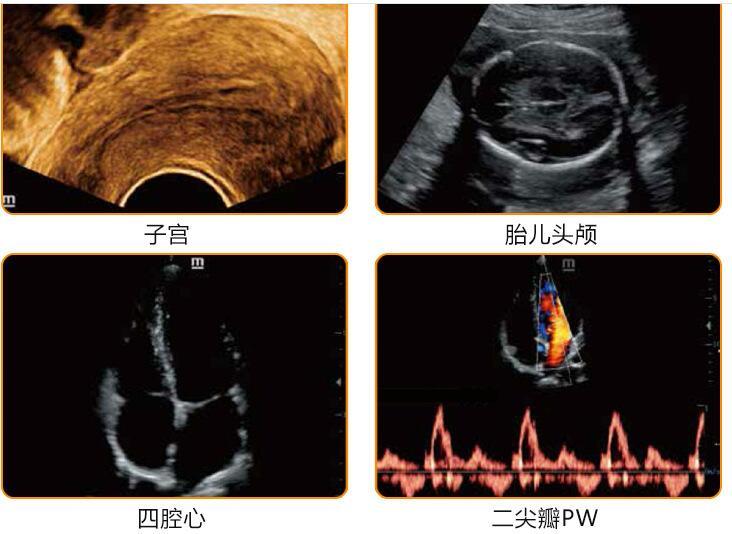

使用甘道夫宠物B超小动物B超彩超可以快速检测猫狗等常见宠物是否怀孕成功胎子数量和宠物常见的子宫卵巢炎症囊肿结石肿瘤肿块结石等繁殖疾病,快速加快宠物繁殖育种和科学疾病防控诊断水平,随着猫咪、狗狗年龄的增长,当他们发育成熟时,有的主人会选择带它们做绝育手术;也有的主人想把这份可爱的基因延续下去,选择繁育后代。给大家简单介绍一下毛孩子繁育方面的知识。宠物B超厂家小动物B超品牌报价价格大全

使用宠物B超可以对猫狗等宠物孕前孕中孕后实时检测超超声检测,及时发现宠物潜在繁殖障碍疾病早干预早预防,加快宠物繁殖育种改良速度,提升宠物优生优育的质量,宠物病理学 对犬、猫的繁殖的认识经历了一个漫长的过程,即从最初的现象观察和性行 为的描述到解剖学、细胞学的探究。随着相关科学技术的发展和进步,现在已深入到生殖 细胞的显微和超微结构,为了做到对宠物 科学的繁殖、能动的改良和有效的防病,促进宠物健康发展,许多职业院校开设了宠物及 相关专业,宠物繁殖是该专业的一门重要的专业课。为适应社会发展的需要。

一、临床应用:适用于牛、羊、猪等动物的背膘厚度眼肌面积瘦肉率测量计算和妊娠诊断以及卵巢子宫炎症囊肿黄体积水生殖疾病筛查。猫狗羊猪等小动物繁殖育种改良超声诊断和常见生殖疾病筛查诊断。